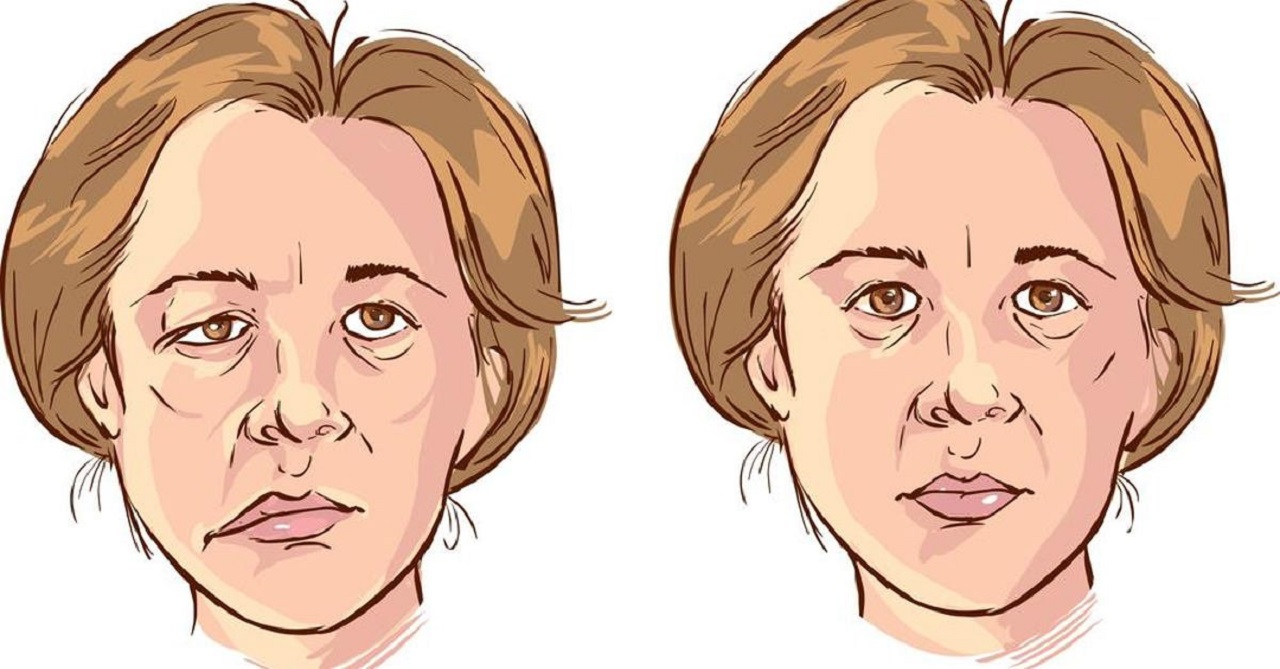

Lệch hàm, lệch mặt